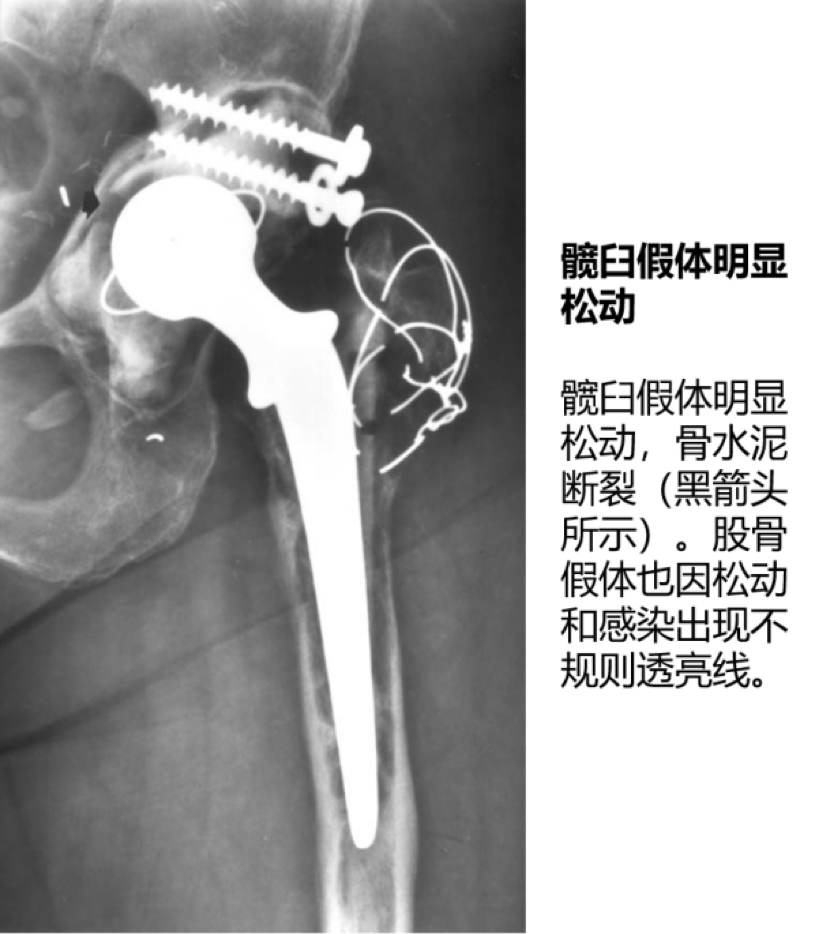

2. 假体无菌性松动:

股骨假体松动发生率为 6%~18%,髋臼假体为 6%~28%。松动是最常见的翻修原因。

影像学特征:

①骨-骨水泥界面/金属-骨水泥界面放射性透亮线大于 2mm;放射性透亮线进行性增宽或不规则;

②股骨假体下沉/移位,髋臼假体移位/内陷;

③假体柄断裂;骨水泥断裂;

④假体表面喷涂材料脱落。

3. 感染:

发病率 2%~3%。